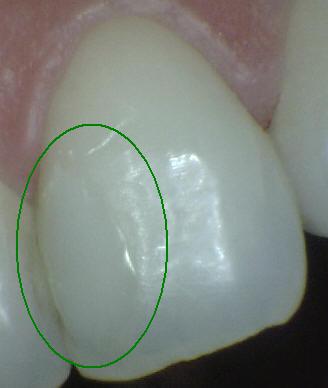

Código 1(Caries

Inicial): Primer cambio

visible en el esmalte seco

- Cuando se observa la

superficie húmeda no hay evidencia de cambio de color

que se pueda atribuir a actividad cariogénica, pero

después del secado prolongado con aire (durante

aproximadamente 5 segundos) se observa una opacidad o

pigmentación compatible con desmineralización que no es

consistente con el esmalte clínicamente sano.

- (Mancha blanca

/ marrón)